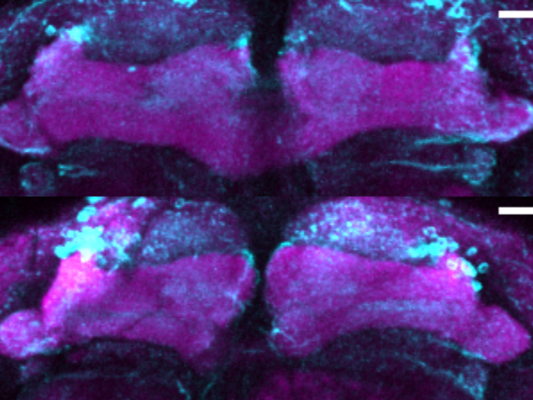

Leuven, January 12, 2026 – Researchers at VIB and KU Leuven have identified a molecular process that allows motor neurons to maintain protein production, a process that fails in amyotrophic lateral sclerosis (ALS). The study, published in Nature Neuroscience, reveals an early weakness in neurodegeneration and highlights a potential target for future therapies.